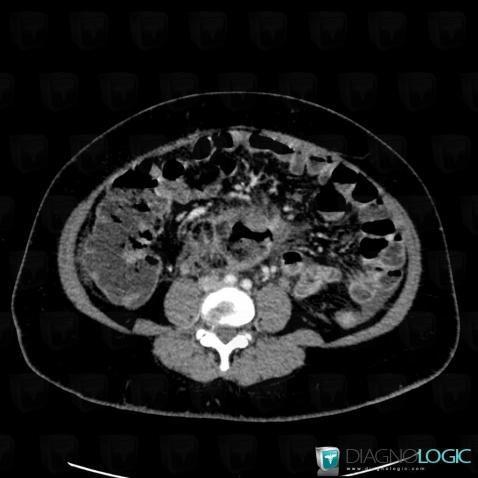

Colon cancer, Colon, CT

Here is the specific information in the key image above:

- Diagnosis Colon cancer, Location(s) Colon, with gamuts Thickening of colon wall, Colonic mass or filling defect